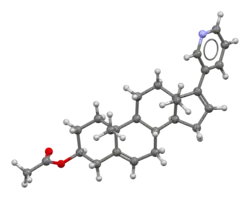

Abiraterone acetate, also known as 17-(3-pyridinyl)androsta-5,16-dien-3β-ol acetate, is a synthetic androstane steroid and a derivative of androstadienol (androsta-5,16-dien-3β-ol), an endogenous androstane pheromone.[41] It is specifically a derivative of androstadienol with a pyridine ring attached at the C17 position and an acetate ester attached to the C3β hydroxyl group.[41] Abiraterone acetate is the C3β acetate ester of abiraterone.[41]